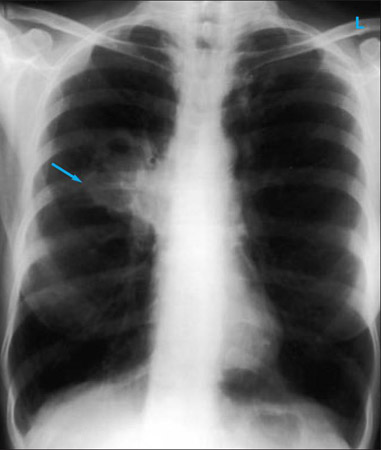

Chest x-ray showing a cavitating right hilar carcinoma (arrow)

E. Dick, Student BMJ. 2001;9:10-12